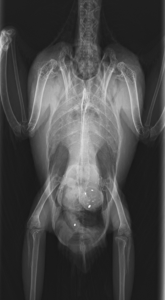

レントゲン検査で胃内に金属陰影が見られたため、発作止めと中毒治療を開始しました。